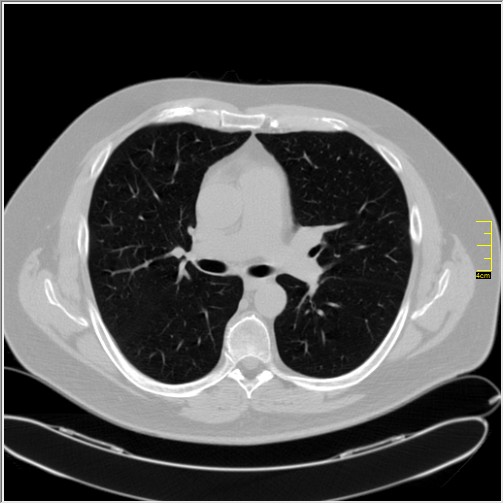

Četiri dana kasnije. Isti pacijent dolazi sa istim pulmologom. Situacija je sada sasvim drugačija. Temperatura 39.5 C. Saturacija 92. Laboratorija daleko gora. Uradim CT pluća. Ovo je izašlo.

Severity score 15/25. Pacijent je upućen na bolničko lečenje.

Ono što zbunjuje, a to se ponavlja zadnjih 10 dana, je da fibroza nastupa u progresivnoj fazi, znači na početku bolesti. Toga nije bilo do sada. Sledećih dana ću o tome.

Ovo je samo 4 dana. Od zdravlja do teške bolesti. Pacijent je 45 godina starosti, očigledno nije povećane težine, kaže za sebe da je bio sportista. U anamnezi nije naveo nikakve bitne bolesti.